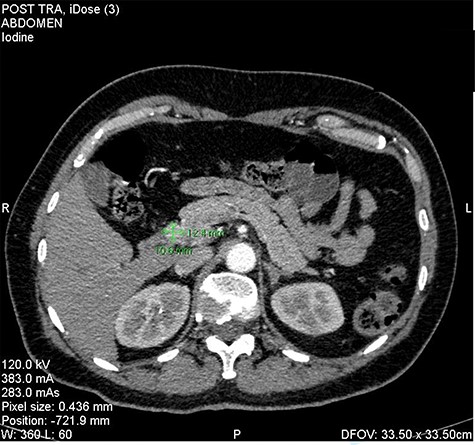

We present the case of 46-year-old female patient suffering from spontaneous hypoglycemia. She was admitted to our hospital due to worsening clinical symptoms. At first, she underwent a 72-hour monitored fast and biochemical testing for endogenous hyperinsulinism, which proved positive. Once the other causes of spontaneous hypoglycemia were excluded, we started the process of localization of insulinoma. Then the patient underwent endoscopic ultrasonography (EUS) of pancreas with the find of hypoechogenic, well demarcated, hypervascular tumor in the head of pancreas size of 12.4 × 10.5 mm (Fig.1). Computed tomography (CT) examination of abdomen followed up and tumor of pancreatic head, corresponding with the diagnosis of insulinoma, was found (Fig. 2). It was located nearby pancreatic and biliary duct. Because of serious clinical symptoms, an early surgical treatment was indicated. Based on the evaluation of the surgeon to perform the less radical surgery, it was suggested to enucleate the tumor with preoperative stenting of pancreatic and biliary duct. Two days before the surgery, ERCP with insertion of pancreatic and duodenobiliary stent was performed (Fig. 3). With regard to the patient's preference and overweight, laparotomic approach was selected. Determination of the exact position of tumor was difficult, insulinoma was hardly palpable. We used intraoperative ultrasonography to identify the exact location of tumor (Fig. 4). Then the surgeon palpated the inserted stents and the insulinoma was identified intrapancreatically, 3–4 mm nearby pancreatic and bile duct. Enucleation of tumor was performed by harmonic scalpel (Fig. 5). During the surgery, the right position of stents was verified by touch. After enucleation, there was no presence of bleeding, the defect was filled with tissue glue (Fig. 6). Macroscopically, tumor was round shaped, well capsulated, size 1 cm (Fig. 7). During postsurgery period, the patient was stable and with no signs of complication. On the sixth postoperative day, endoscopic removal of pancreatic stent was carried out. Patient was discharged from the hospital on the eight postoperative day. Duodenobiliary stent was left in ductus choledochus for 1 month.

Insulinoma in the head of the pancreas—CT picture in arterial phase (as shown green marks).